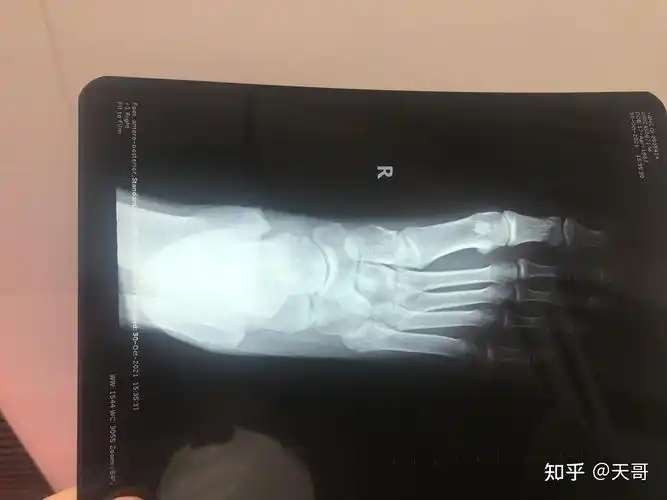

右足跟骨骨折

右脚第五跖骨基底骨折